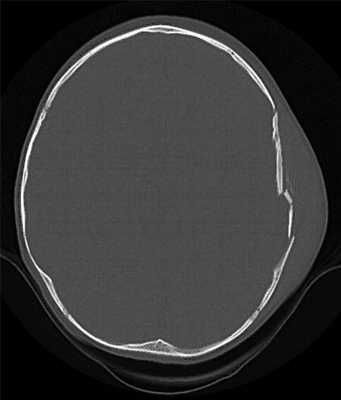

Применение компьютерной томографии в нейротравматологии существенно изменило представление о возможностях диагностики различных черепно-мозговых повреждений. КТ является в настоящий момент «золотым стандартом» - наиболее информативным методом обследования больных с черепно-мозговыми травмами и позволяет в самые короткие сроки судить о механизмах возникновения поражения мозга, его характере, распространенности, выраженности отека и дислокации мозга, а также динамике этих изменений.

КТ позволяет последовательно изучить мягкие ткани головы, кости черепа, вещество мозга, эпидуральные, субдуральные, субарахноидальные пространства, цистерны основания и желудочки мозга:

- выявить переломы свода и основания черепа (с чувствительностью, намного превышающей традиционную рентгенографию) ,

Визуализация минимальных количеств излившейся свежей крови, уверенная дифференциация ее от других внеклеточных жидкостей, слежение за динамикой отека и набухания головного мозга, некроза и восстановления его структур с одновременным распознаванием переломов костей черепа, особенно его основания, составляют преимущества КТ перед магнитно-резонансной томографией.